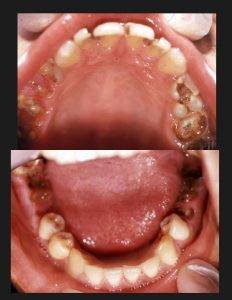

唐突であるが、これは18歳の悲惨な少年の口腔である。(図1)

図1

この歯では、せいぜい前歯でうどんを咬み切って、丸飲みする位の食べ方しかできないだろう。

さて、冒頭で18歳の少年の写真をご覧いただいた。

この写真、実は少年院で撮影したものである。

重い罪を犯した、多くの少年達は、このような口をしていた。